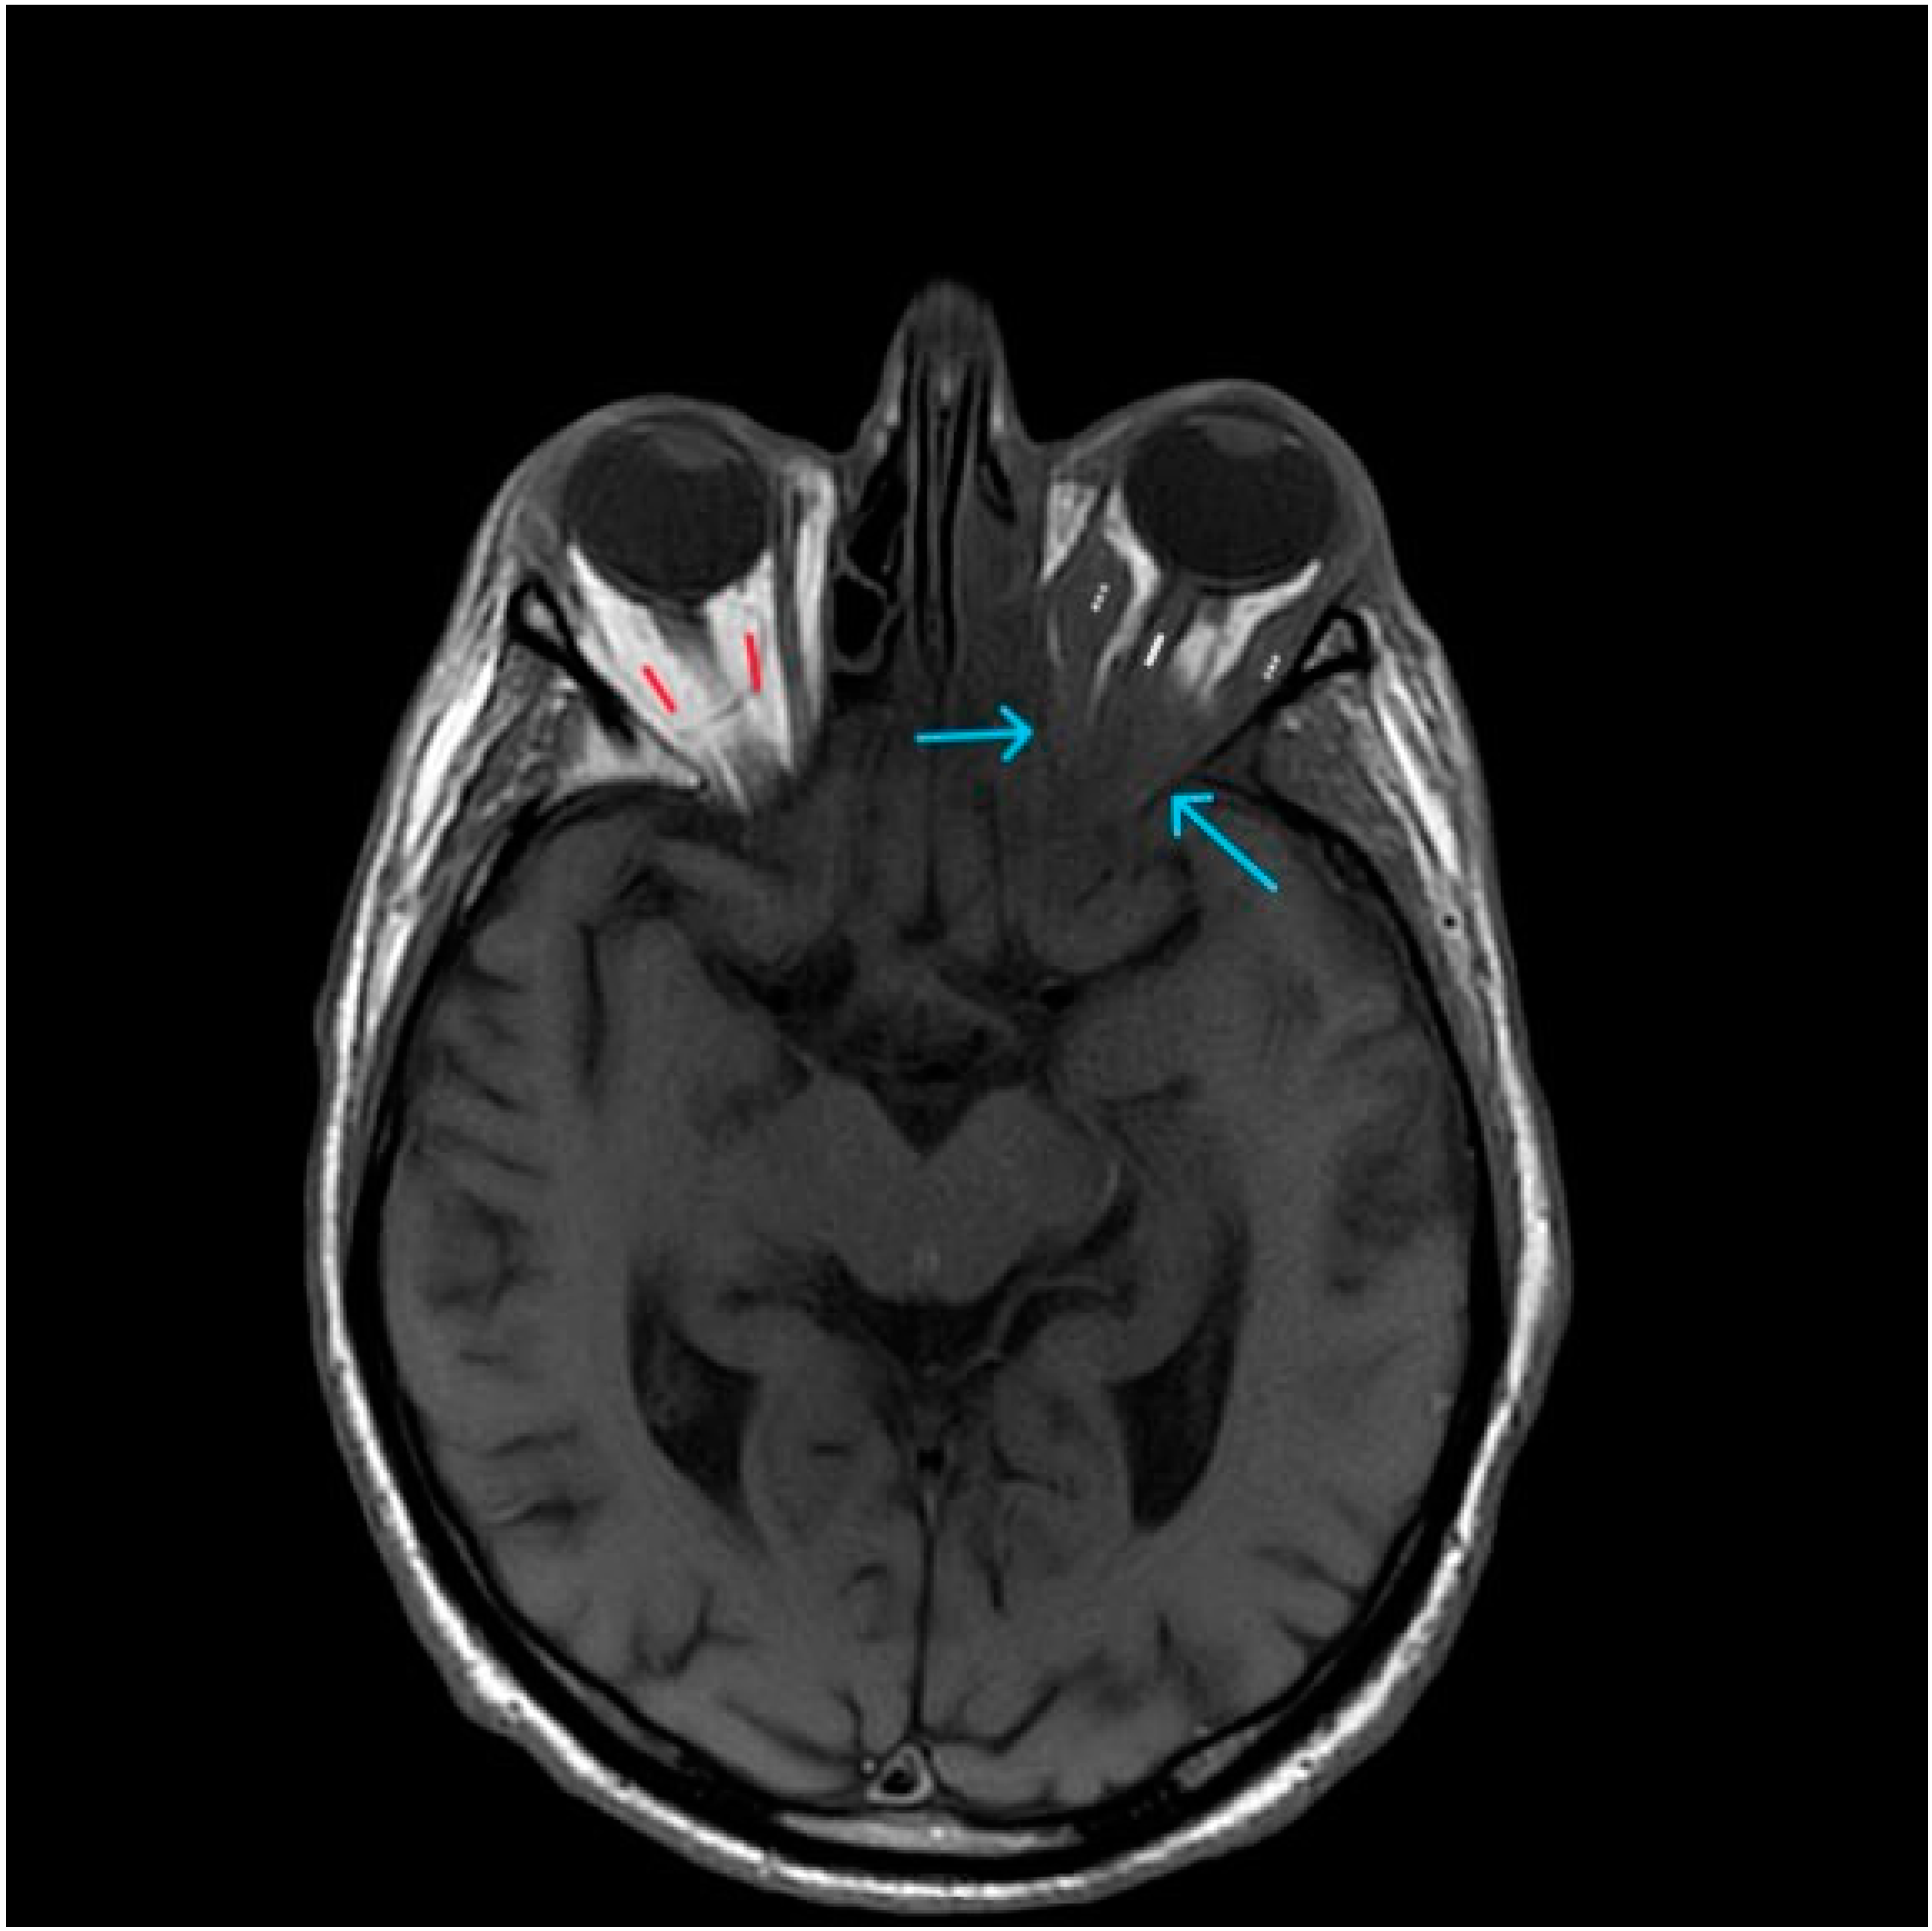

Figure 3. Axial T1-weighted image at the level of the orbits. Arrows are pointing at the reduced intraconal fat tissue due to intracranial extension of the pathological process in the left maxillary sinus. White line—optic nerve. Dots—medial and lateral oculomotor muscles. Red—normal hyperintense (white) fat tissue of the intact orbit.